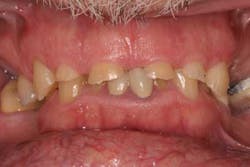

Case study A 58-year-old male with a noncontributory medical history presented to a private practice for a complete rehabilitation of his dentition due to years of bruxism and parafunction. (Fig. 1) After surgical and restorative consultations, a treatment plan was fabricated. The treatment plan included restoring his lost vertical dimension, restoring his natural dentition with porcelain-fused-to-metal full-coverage crowns, and replacing his lost posterior teeth with dental implants. After his vertical dimension was restored with an acrylic bite plate to a position harmonious with TMJ function, crown-lengthening surgery was performed. (Fig. 2)Fig. 2 Six weeks after, the teeth were temporized to develop soft tissue margins/interdental papillae. (Figs. 3 and 3a) The patient was kept in temporaries for three months, during which time an implant was placed in site No. 19. Both the natural dentition and the implant were completed at the same time, three months after implant placement. (Fig. 4) Because of the patient’s occlusal issues, the implant was screw-retained, and the patient was given a maxillary night guard. Three weeks after insertion, the patient presented with a loose abutment screw. The dentist tightened the screw and sent the patient home. This cycle was repeated two more times until the patient presented again with a loose crown, but this time, a fracture implant screw. The dentist attempted to remove the screw with a Cavitron and drilling the implant screw out to release preload, but to no avail. The case was then referred to my office for implant removal.